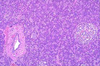

2

Q

A

Liver